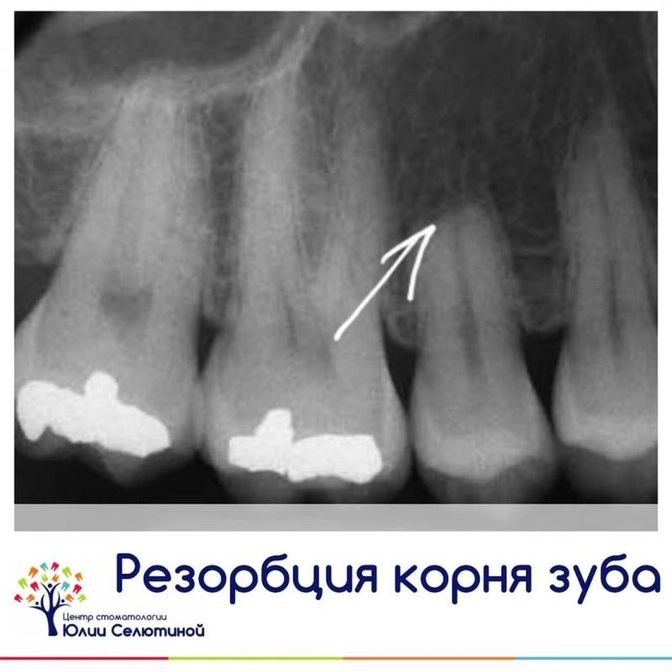

Резорбция корней зубов.

Резорбция (или рассасывание) корня - это патологический процесс убыли тканей корня и околокорневых тканей (костной, периодонта, цемента корня, дентина, пульпы).

• Внутреннюю - очень часто идет бессимптомно.

Возникает при повреждении пульпы зуба или сосудисто-нервного пучка, тем самым идет перерождение этих тканей в гранулематозную, и грануляция постепенно ведет к рассасыванию тканей зуба.

Диагностируется с помощью снимка либо на КТ.

Внутреннюю резорбцию часто находят внезапно на снимке и пациент даже не подозревает, что корень уже начал рассасываться.